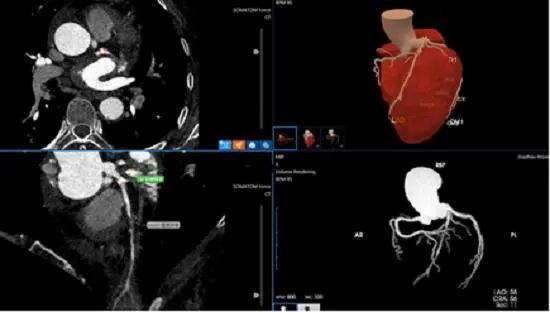

6月21日,筆者從貴州省人民醫(yī)院獲悉,該院醫(yī)學影像科診斷醫(yī)生近日運用人工智能醫(yī)療技術僅用5分鐘,就為一名左前降支重度狹窄患者作出準確診斷,經(jīng)人工智能輔助診斷冠心病技術快速準確診斷為冠心病。確診后,在貴州省人民醫(yī)院心內科施行冠狀動脈介入治療后,目前該患者術后恢復良好。